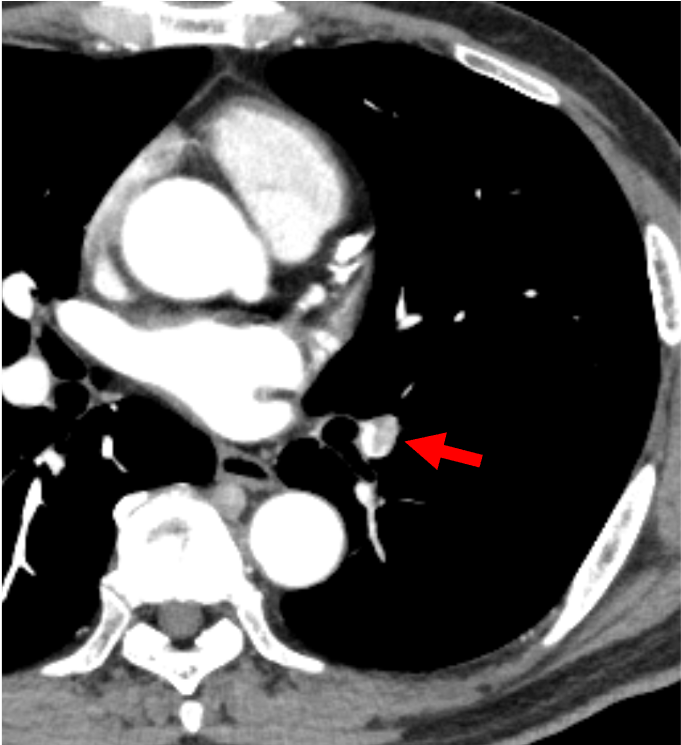

右腎には、実質を置換性に広がる早期濃染とwashoutを示す腫瘍を認め、腎細胞癌と考えられた。腫瘍は腎静脈を経て下大静脈に進展し横隔膜レベルに達していた。また左腎動脈には低造影域を認め、肺動脈腫瘍栓と考えられた。

腎腫瘍の診断において、ダイナミック造影CTはその組織型の推定に有用である。腎腫瘍の多くの割合を占める通常型(淡明細胞型)腎細胞癌は、早期相で周囲の腎皮質と同程度に濃染し(早期濃染)、後期相では周囲に比してやや低造影を示す(washout)ことが特徴である。さらに、腫瘍増大に伴い、本症例のように腎静脈や下大静脈へ進展が見られやすいのも特徴の一つと言えるだろう。また、本症例では腎動脈に塞栓を疑う低造影域を認めた。多くは血栓塞栓であり、その場合は原因となる下肢静脈血栓の有無を検索する必要がある。しかし、本症例では肺動脈内病変には斑な造影効果を認め、FDG-PET(非提示)では集積像を示した。静脈内進展を伴う腎腫瘍の存在と合わせて肺動脈腫瘍栓と診断した。肺動脈塞栓を認めた場合には、血栓以外の可能性についても一考することが大切である。